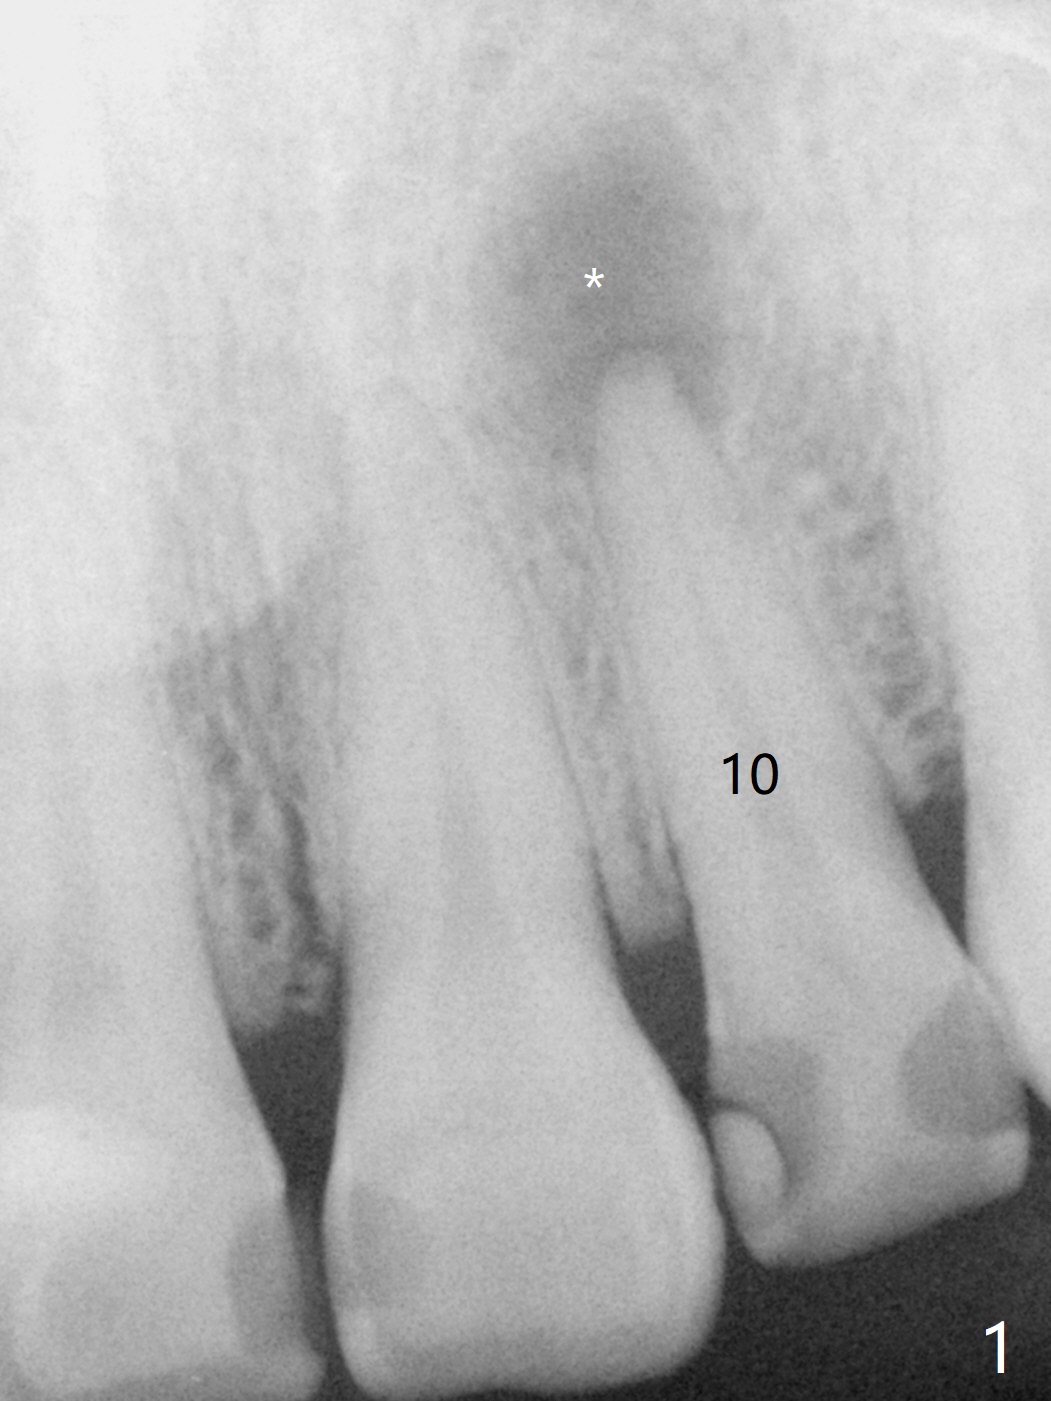

A 47-year-old woman with multiple restoration has PARL at #10 (Fig.1 *). RCT is done with paste leakage (Fig.2). PARL reduces and disappears 2.5 and nearly 10 years postop (Fig.3,4).